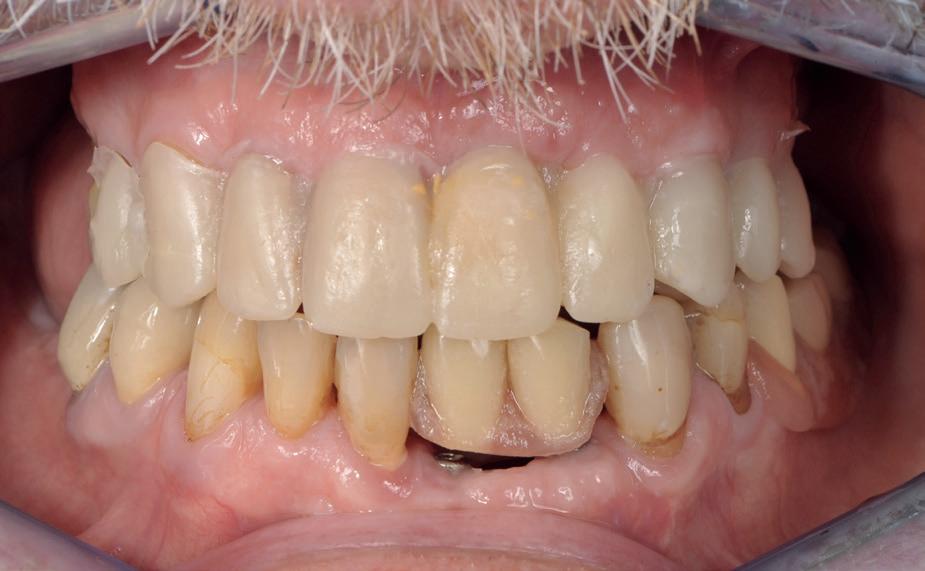

De patiënt, een 70-jarige man, had in het verleden tandheelkundige zorg ontvangen die zich kenmerkte door een ad hoc benadering. Er was geen sprake van een overkoepelend behandelplan of lange termijnvisie. De patiënt had naar eigen zeggen jarenlang niets

1. Studiofoto intake

aan zijn gebit gedaan behalve pappen en nathouden. Tandheelkundige zorg werd enkel verleend wanneer er zich een probleem voordeed (afbeelding 1, 3, 5).

De patiënt werd in de eerste fase gezien door de parodontoloog, implantoloog en restauratief behandelaar. Klinisch werden drie complicerende factoren vastgesteld: inadequate mondhygiëne, een ongunstige occlusale relatie en restauraties met gebrekkige marginale adaptatie met overhang. De patiënt werd opgenomen in het parodontale behandelprotocol.

De diagnose luidde lokaal parodontitis met ernstige furcatie aandoeningen; Stadium IV (vergevorderd); graad C (snel progressief) (afbeelding 7) De elementen die niet te behouden waren, werden geëxtraheerd.

Tijdelijke voorzieningen werden getroffen in de vorm van een etsbrug in de bovenkaak en een uitneembare voorziening voor de onderkaak.

Na afronding van de eerste twee behandelstappen werd parodontale stabiliteit bereikt, zoals waarneembaar op de parodontiumstatus en (röntgen)foto’s (afbeelding 6, 8). De patiënt toonde aantoonbare verbetering in mondhygiëne (afbeelding 4) en bleef gemotiveerd om de behandeling voort te zetten.